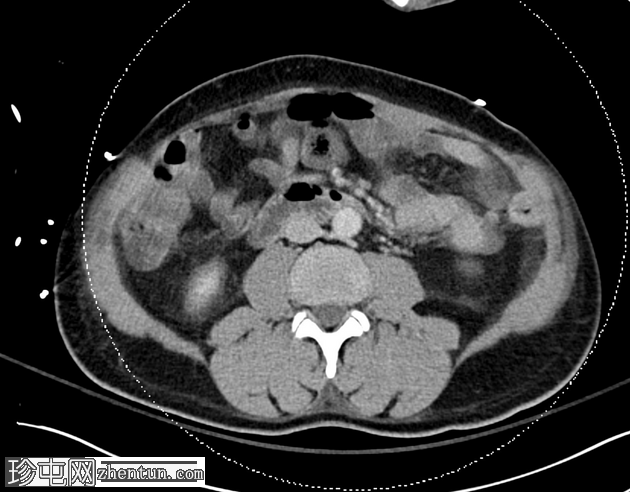

轴向C+门静脉期

小脐疝伴Richter疝,包含小肠前壁(肠系膜对侧部分),无梗阻或并发症。